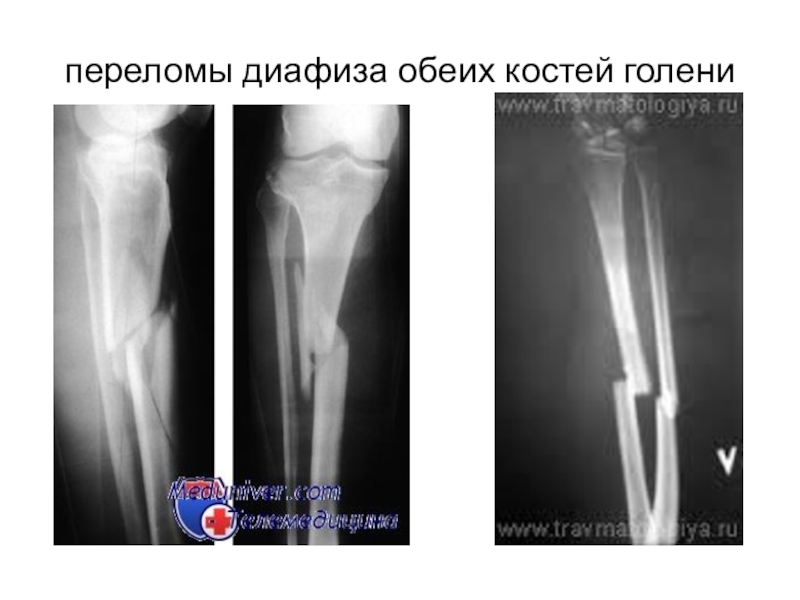

Слайд 35переломы диафиза обеих костей голени

переломы диафиза обеих костей голени